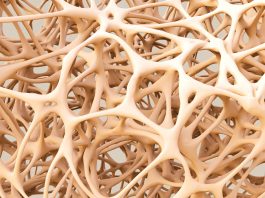

Often used in spinal surgery, polyether ether ketone is showing promise as a material tubular and as a flat bones implant. In this case, it is necessary to ensure a strong fusion of the polyether ether ketone with the patient’s bone. This fusion requires additional processing of the material to create a porous structure in which the bone tissue would grow.

The research team have now developed a combinatory approach to creating implants. The approach suggests the use of polyether ether ketone in the production of a porous implant. Researchers also explored the possibility of combining polyether ether ketone with hydroxyapatite, which is the main mineral component of bone tissue, as well as two proteins, erythropoietin (EPO) and bone morphogenetic protein BMP-2.

“After thermal pressing, the samples were washed to dissolve the salt. As the result, we had a material with 80% porosity”, comments Alexander Chubrik, one of the authors of the study.

Researchers formed the structure using salt crystals of two sizes, 106-200µm and 40-75µm. The first size allowed scientists to form pores in the material, the second created a microrelief on their surface. If the pores are needed more for the sprouting of blood vessels and bone tissue, the microrelief contributes to the attachment of osteoblasts to the surface of the implant.